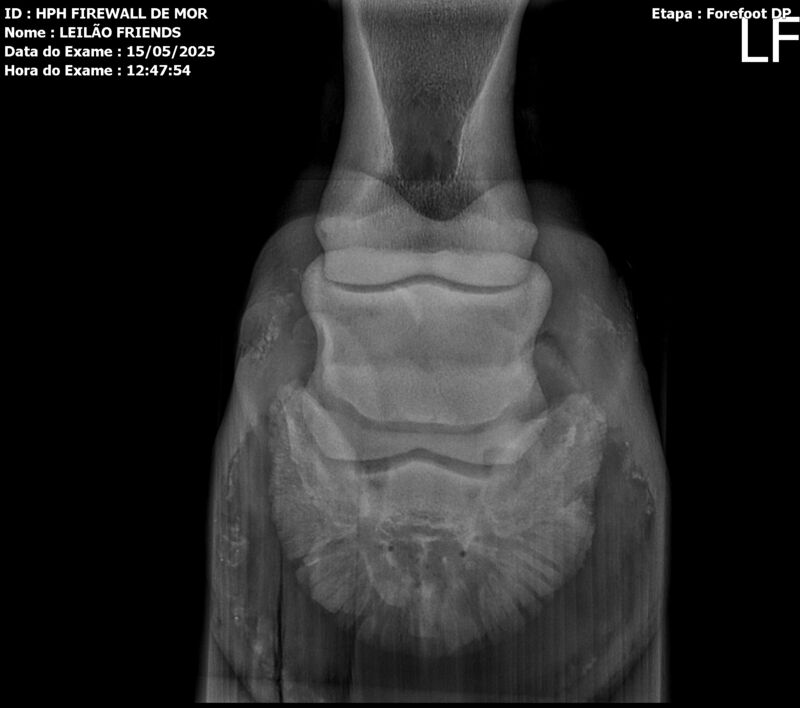

Sexo: MACHO

Nascimento: 13/04/2023

Pelagem: TORDILHA

Altura aproximada: 1,61m

Previsão de altura: 1,66m

Vendedor: HARAS HPH / TRV

Localidade: SÃO PAULO/SP

Garanhão tordilho, apesar de jovem, mostra muito poder e uma plástica de salto incrível. Firewall é sempre muito positivo, busca o salto e os supera com muita agilidade e leveza.